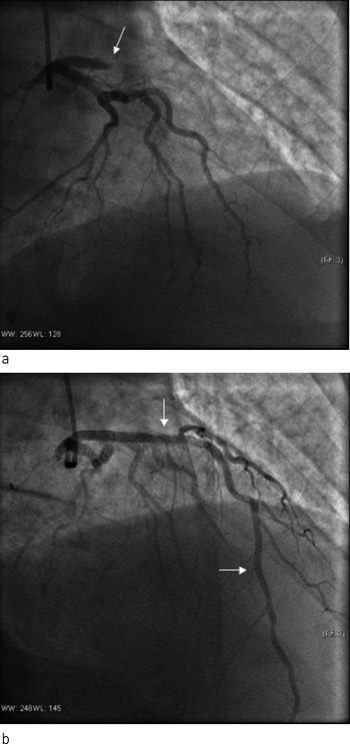

Nytt EKG viste nytilkomne ST-hevninger i fremreveggsavledningene som ga mistanke om reokklusjon av behandlet koronararterie. Ny koronarangiografi viste okkluderende trombe ved inngangen til stenten og i hele det tidligere stentede området (fig 1). Man valgte å gi ufraksjonert heparin og abciximab (en glykoprotein IIb/IIIa-hemmer) samt utføre ny PCI med stenting av proksimale venstre fremre koronararterie. Det angiografiske resultatet var godt, pasienten ble raskt smertefri og det tilkom ingen ny økning i CK eller troponin T.

Det ble besluttet å seponere klopidogrel en uke etter infarktet pga. fare for stor blødning og blæretamponade. Lokalsykehuset valgte å beholde acetylsalisylsyre og lavmolekylært heparin, da man mente at en potensiell stor urinveisblødning var lettere å håndtere ved denne kombinasjonen enn ved bruk av klopidogrel. Det ble planlagt transurethral biopsi og tumorreseksjon etter noen dager. Dag 11 etter første hjerteinfarkt ble pasienten forsøkt overflyttet til sykehus med urologisk senter for biopsitaking. Under ambulansetransporten fikk pasienten på nytt sterke brystsmerter, og EKG viste nye ST-hevninger i fremreveggsavledninger. Transporten ble avbrutt og pasienten ble i stedet fraktet til Oslo universitetssykehus, Ullevål for ny akutt koronarangiografi. Her fant man for andre gang en nytilkommet trombotisk okklusjon av stenten i venstre fremre koronararterie. Det ble utført ballongdilatasjon med implantasjon av konvensjonell metallstent. Klopidogrel ble gjeninnsatt, mens lavmolekylært heparin ble seponert. Man ga ufraksjonert heparin under prosedyren, men ikke glykoprotein IIb/IIIa-hemmer. Denne gangen var troponin T-verdien 2 µg/l, hemoglobin 11 g/dl og trombocytter 160 x 10⁹/l.

Pasienten ble flyttet tilbake til lokalsykehuset i påvente av koronaroperasjonen. Dag 14 fikk pasienten nye smerter og EKG-forandringer forenlig med okkludert venstre fremre koronararterie. Han ble på ny overflyttet til Oslo universitetssykehus, Ullevål, der det for tredje gang ble påvist stenttrombose. Okklusjonen ble åpnet med ballongdilatasjon uten ny stentimplantasjon. Han fikk ufraksjonert heparin og abciximab under prosedyren. En time etter avsluttet prosedyre tilkom spontanblødninger fra nese, gastrointestinalkanalen, urinveier og alle innstikksteder på kroppen. Blodprøvene viste nå trombocyttverdi 2 x 10⁹/l, som var en drastisk nedgang fra verdien målt tidligere samme dag på lokalsykehuset (187 x 10⁹/l) (fig 2). Troponin T-verdien var 3,2 µg/l og hemoglobinnivået 13,1 g/dl, synkende til 9,8 g/dl. Abciximab ble øyeblikkelig seponert. Han fikk deretter totalt fire enheter platekonsentrat, og man «nullet ut» klopidogrel. Ved denne behandlingen steg trombocyttene til ca. 60 x 10⁹/l og deretter spontant til 136 x 10⁹/l. Etter stabilisering av situasjonen valgte man å gi heparin som kontinuerlig infusjon. Dette var vellykket. Trombocyttallet fortsatte å stige. Pasienten gjennomgikk koronaroperasjon med bruk av hjerte-lunge-maskin og heparin 20 dager etter første hjerteinfarkt. Han ble utskrevet til sitt lokalsykehus for videre oppfølging av koronarsykdom og mistenkt kreftsykdom. Tumoren i urinblæren viste seg å være et lavgradig, malignt karsinom uten muskelinvasivitet, og radikalbehandling er under planlegging.